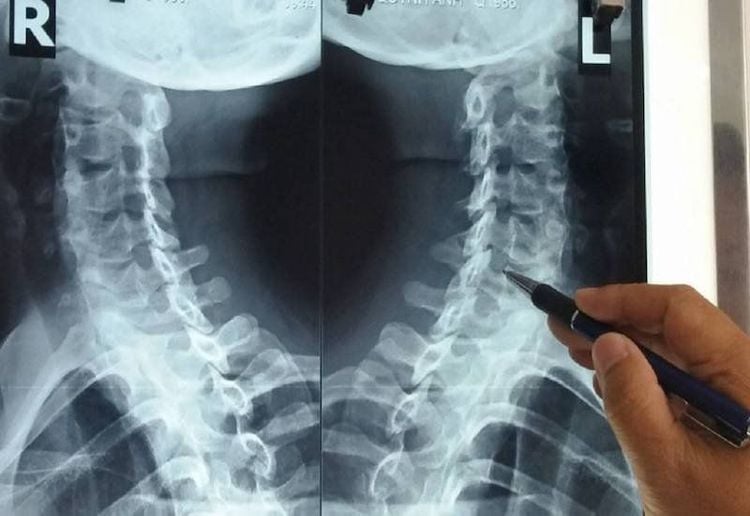

Theo Science Direct, trật khớp cột sống cổ là một tổn thương nghiêm trọng của cột sống cổ, trong đó các đốt sống bị lệch khỏi vị trí bình thường. Đây thường là kết quả của chấn thương mạnh do tai nạn, té ngã, va đập trong thể thao hoặc tai nạn giao thông.

Tổn thương này thường đi kèm với gãy xương và ảnh hưởng đến cấu trúc ba cột của cột sống, gây mất ổn định cột sống và nguy cơ nghiêm trọng cho tủy sống.

Bi Rain thừa nhận đang mắc thêm một căn bệnh nguy hiểm- Ảnh 3.

Ảnh minh hoạ